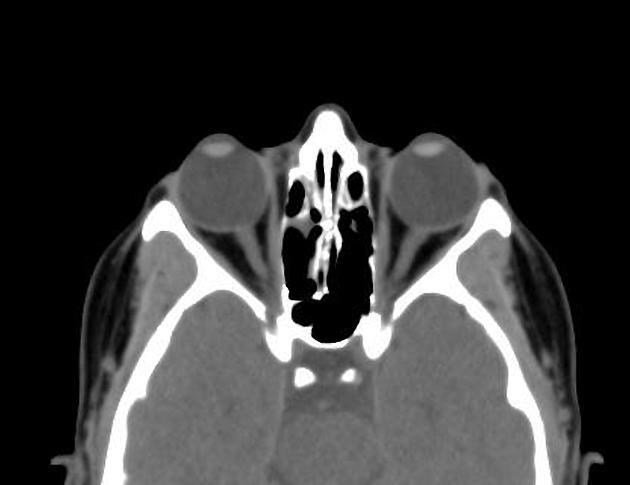

5) Orbit CT

시신경, rectus muscles, lens, 초자체, 정맥, 연조직 등을 본다.

Orbit CT - Google 검색

Radiology Anatomy Images :... radiology-anatomy.blogspot....